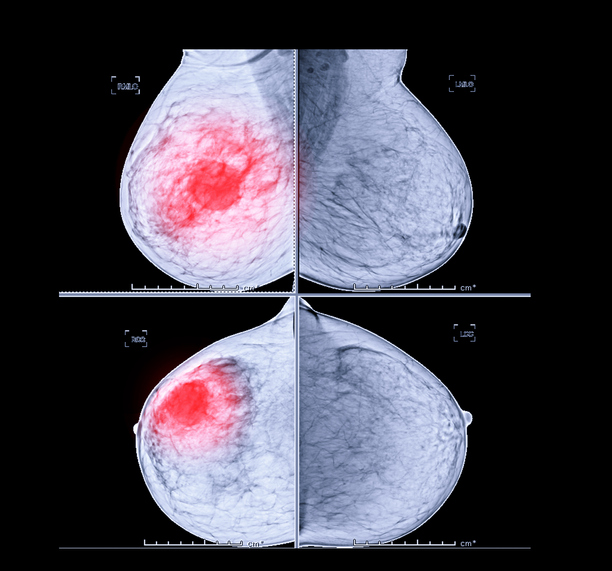

전 세계 여성 3명 중 1명이 암에 걸린다고 알려진 유방암에 좋은 음식과 유방암에 나쁜 음식에 대해서 살펴보도록 하겠습니다. 유방암은 갑상선암에 이어 여성에게 두 번째로 흔한 암이며, 중년 여성의 암 사망률 1위입니다.

유방암은 유방에서 발생하는 모든 악성 종양의 그룹이라고 합니다. 유방암은 유방의 비정상적인 조직이 계속 자라거나 다른 장기로 퍼지는 위험한 질병이라고 합니다. 가장 두드러진 원인은 DNA 손상 및 유전자 돌연변이와 같은 유전적 조건입니다.